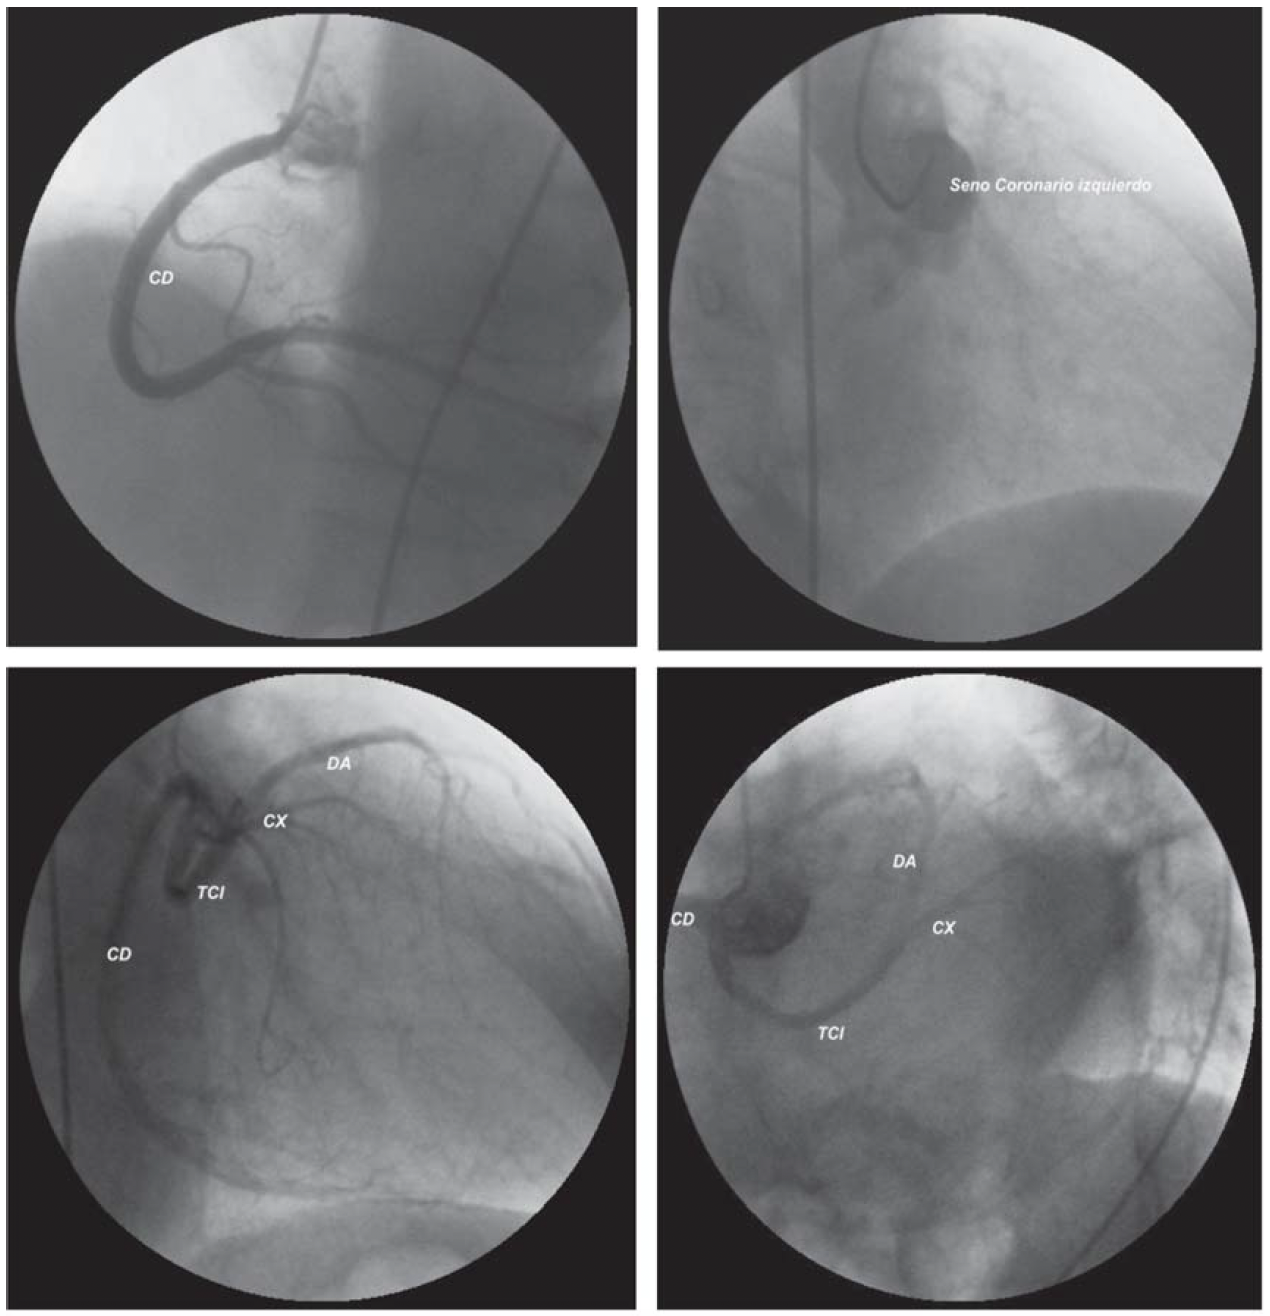

Origen anómalo del tronco de la arteria coronaria izquierda

IMÁGENES EN CARDIOLOGÍA